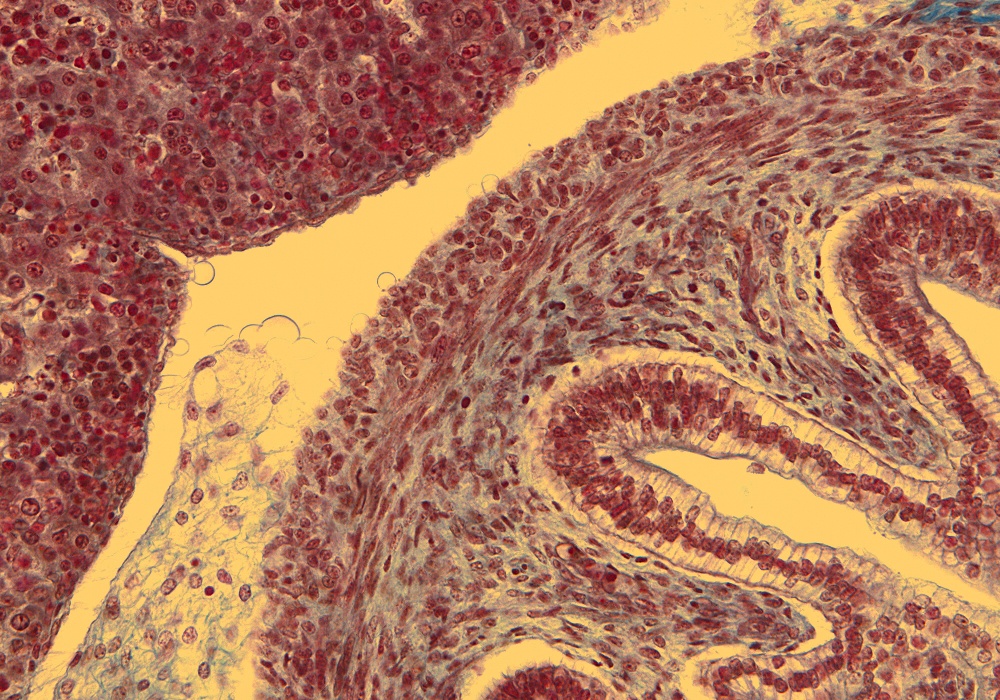

Tissue

–

Duodenum Wall

Carnegie Embryo #9226

Location:

165-01-01